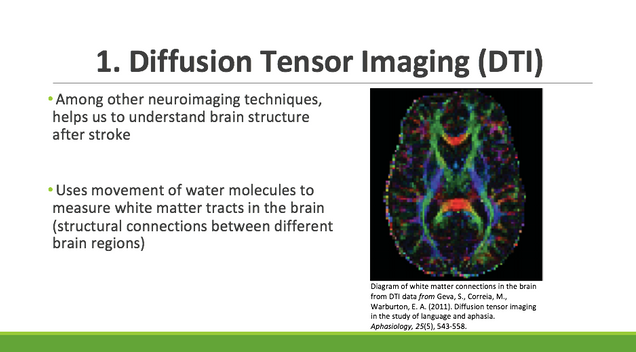

Diffusion Tensor Imaging (DTI)

diffusion, tensor, imaging, DTI, neural markers, MRI, language

Diffusion MRI, also referred to as diffusion tensor imaging or DTI

Diffusion MRI, also referred to as diffusion tensor imaging or DTI